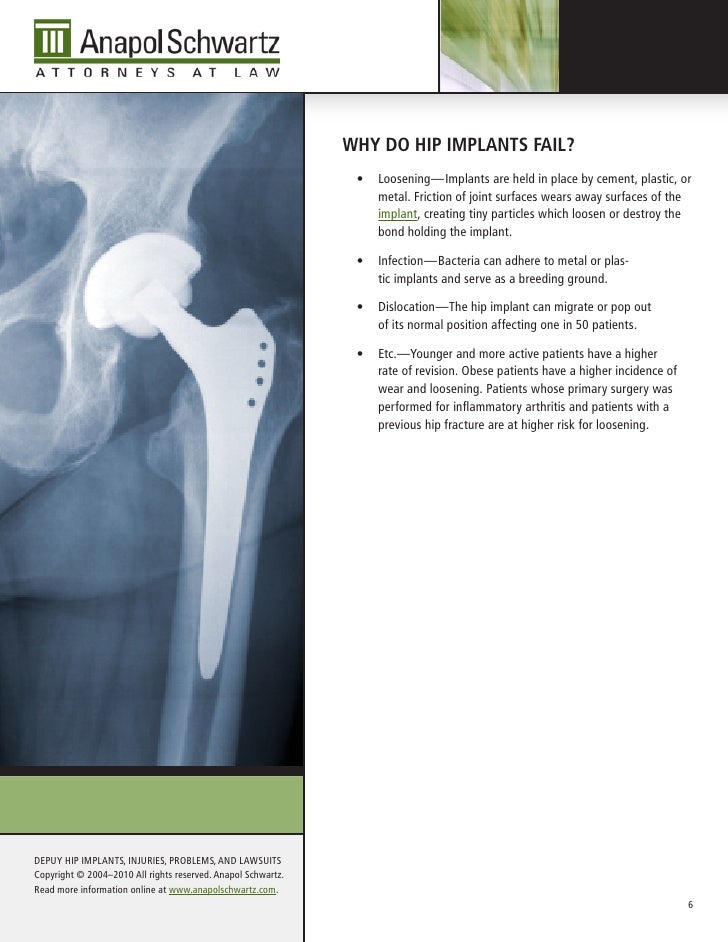

DePuy Hip Implant Recall Lawsuits Hip Replacement Recalls The fda is getting the word out regarding a recall effort from zimmer biomet related to its discontinued cpt hip implant and. Causes for hip replacement recalls include design flaws, early implant failure and migration issues. Hss informs patients who received exactech hip implants between 2004 and 2021 that they may be affected by a recall due to packaging issues.. Hip Replacement Recalls.